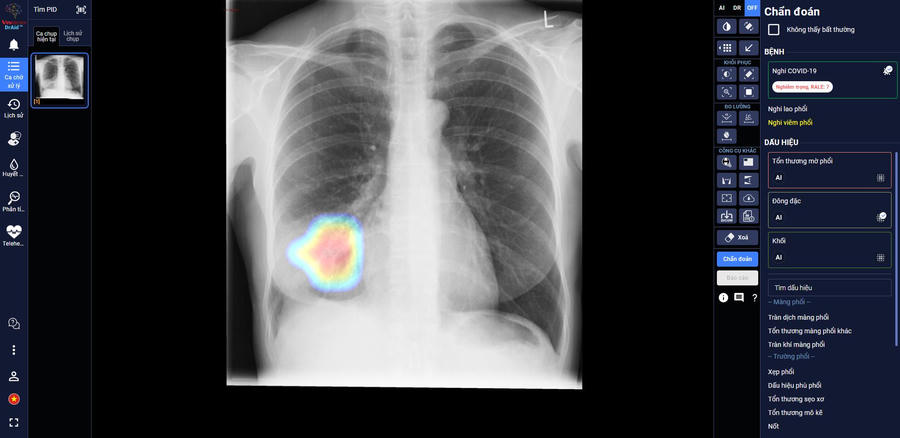

Sau hơn 1 năm nghiên cứu và phát triển, mới đây, VinBrain đã chính thức hoàn thiện sản phẩm DrAid cho COVID-19 với khả năng giải toàn diện bài toán COVID-19 từ hỗ trợ chẩn đoán tới tiên lượng điều trị dựa trên ảnh X-quang ngực thẳng

Trong các bệnh viện thu dung điều trị COVID-19, DrAid cho COVID-19 giúp các bác sĩ đánh giá mức độ tổn thương phổi của bệnh nhân COVID-19 qua các ngày, từ đó đưa ra các chỉ định điều trị kịp thời và hiệu quả cho bệnh nhân.

Theo đánh giá của các bác sĩ tại Trung Tâm Y Tế Kỳ Anh – Hà Tĩnh, AI đã giúp đỡ các bác sĩ khá nhiều khi theo dõi tổn thương qua các ngày, nhận diện rõ ràng là tổn thương lan rộng như thế nào. Ngoài ra, AI cũng giúp bác sĩ nhận diện các tổn thương nhỏ dễ bỏ sót.